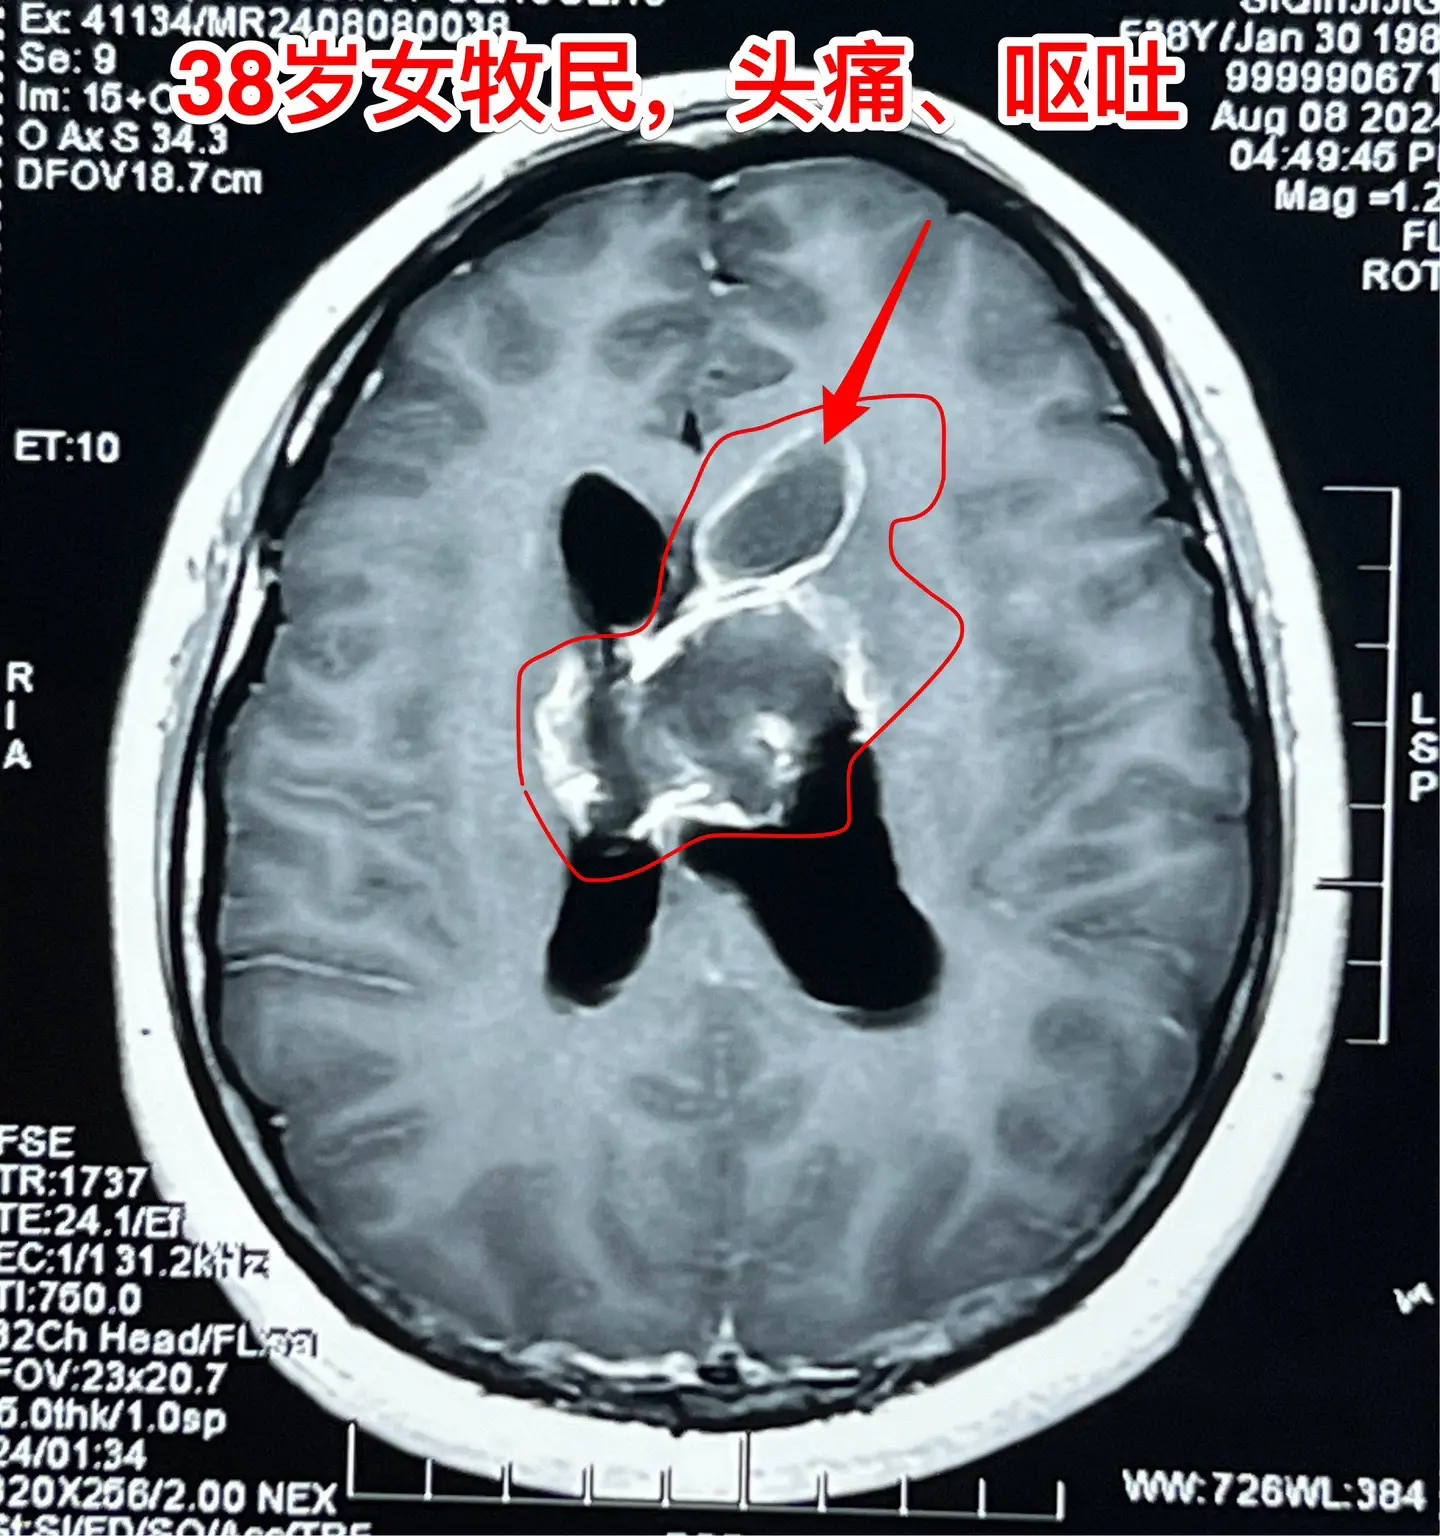

38岁女性脑部发现肿瘤、平时心跳很慢。38岁女性,西乌珠穆沁旗牧民,因头痛、呕吐10天,在锡林浩特市检查发现脑部肿瘤,遂到北京三博脑科医院来作手术。 脑部肿瘤见图,考虑是胶质瘤,肿瘤起源于胼胝体,胼胝体受肿瘤侵蚀,手术前病人的语言和智能没有明显障碍。 在手术准备过程中,发现 病人的心跳很慢,平常才41次/分,夜间最慢慢到31次/分。诊断为窦性心动过缓,为了确保手术安全,不得不临时安放心脏起搏器。 8月9日顺利完成肿瘤切除手术。手术过程很顺利。术中快速冰冻病理报告为胶质母细胞瘤。术后病人很快就清醒了。术后四肢活动无障碍,语言能力和智能情况需要详细评估。